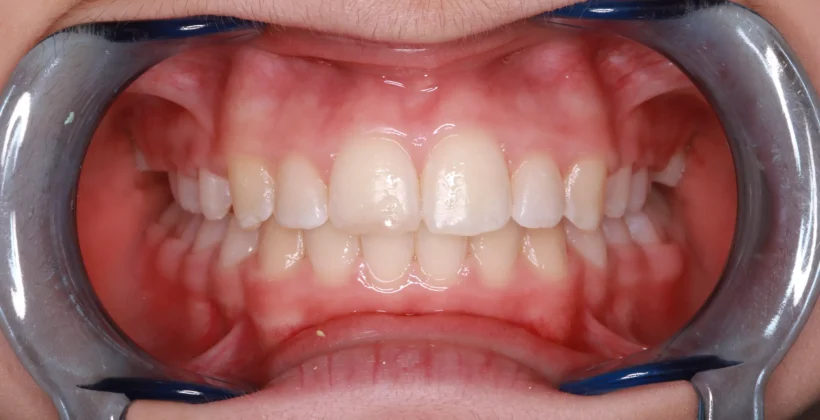

Kezelés után

A fém, rögzített fogszabályzó felragasztását követően havonta találkoztunk aktiválások alkalmával. A fogszabályozóval való kezelés 14 hónapig tartott, ez idő alatt még egyszer részt vett dentálhigiéniai kezelésen. A rögzített készülék levételét követően végül egy fix és kényelmes retainert kapott a fogak belső felszínére, valamint egy kivehető retenciós sínt is átadtunk, melyekkel az elért eredmény rögzülését és megtartását segítjük.